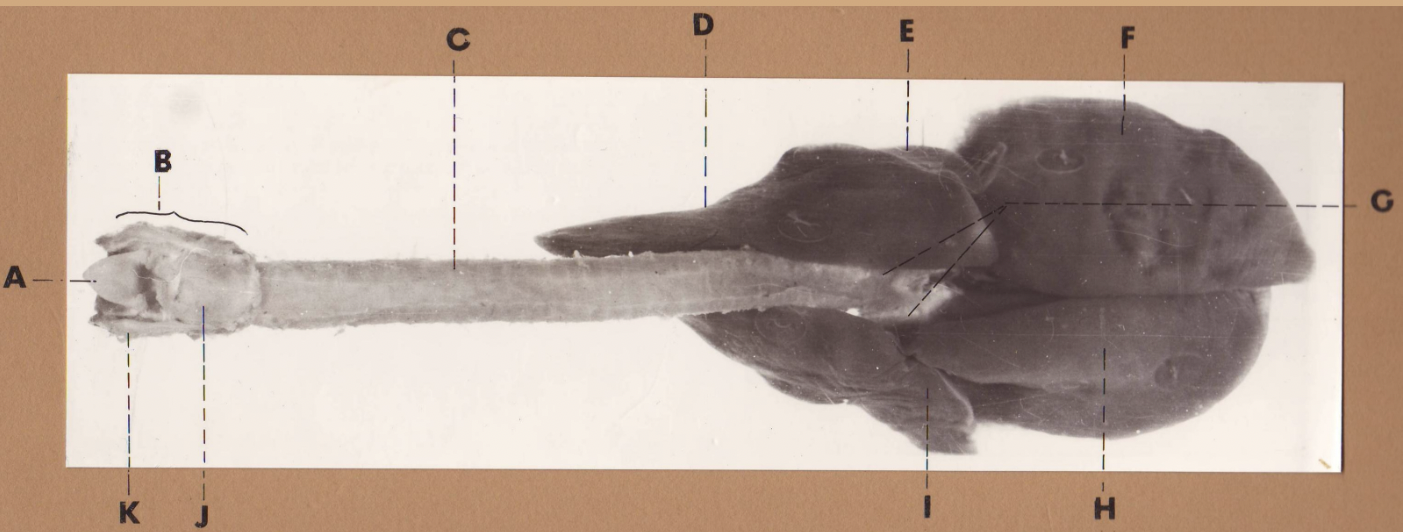

A

(cat larynx/trachea/lungs, dorsal)

epiglottis

B

(cat larynx/trachea/lungs, dorsal)

larynx

C

(cat larynx/trachea/lungs, dorsal)

trachea

D

(cat larynx/trachea/lungs, dorsal)

R cranial lobe

E

(cat larynx/trachea/lungs, dorsal)

middle lobe

F

(cat larynx/trachea/lungs, dorsal)

R caudal lobe

G

(cat larynx/trachea/lungs, dorsal)

primary bronchi

H

(cat larynx/trachea/lungs, dorsal)

L caudal lobe

I

(cat larynx/trachea/lungs, dorsal)

L cranial lobe

J

(cat larynx/trachea/lungs, dorsal)

cricoarytenoideus dorsalis m

K

(cat larynx/trachea/lungs, dorsal)

thyroid

A

(cat larynx/trachea/lungs, dorsal)

epiglottis

B

(cat larynx/trachea/lungs, dorsal)

larynx

C

(cat larynx/trachea/lungs, dorsal)

trachea

D

(cat larynx/trachea/lungs, dorsal)

R cranial lobe

E

(cat larynx/trachea/lungs, dorsal)

middle lobe

F

(cat larynx/trachea/lungs, dorsal)

R caudal lobe

G

(cat larynx/trachea/lungs, dorsal)

primary bronchi

H

(cat larynx/trachea/lungs, dorsal)

L caudal lobe

I

(cat larynx/trachea/lungs, dorsal)

L cranial lobe

J

(cat larynx/trachea/lungs, dorsal)

cricoarytenoideus dorsalis m

K

(cat larynx/trachea/lungs, dorsal)

thyroid